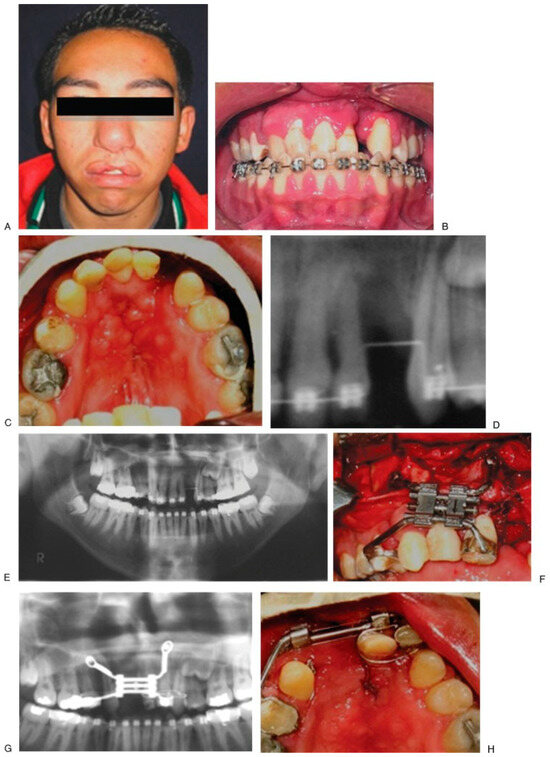

Figure 4. Initial aspect (A–D). There is no anchoring of dental bands, but orthodontic tubes (E). End trifocal alveolar bone transportation technique (F). Aspect at 90 weeks of follow-up (G,H), and radiographics with evidence of closure fissure and osseointegrated implant in the regenerated new bone (I–K). - Case 3 was a 19-year-old male patient with sequel of cleft lip and palate and active oronasal fistula, treated with bifocal ABT (Figure 5).

Figure 5. Initial aspect of the patient; fistula between 9–11 (A–E); alveolar bone transportation technique. Modified Hyrax device (VEGAX) (F–H); at 205 weeks of follow-up (I–K). - Case 4 was a 16-year-old male patient with cleft lip and palate sequel, treated with bifocal ABT (Figure 6).